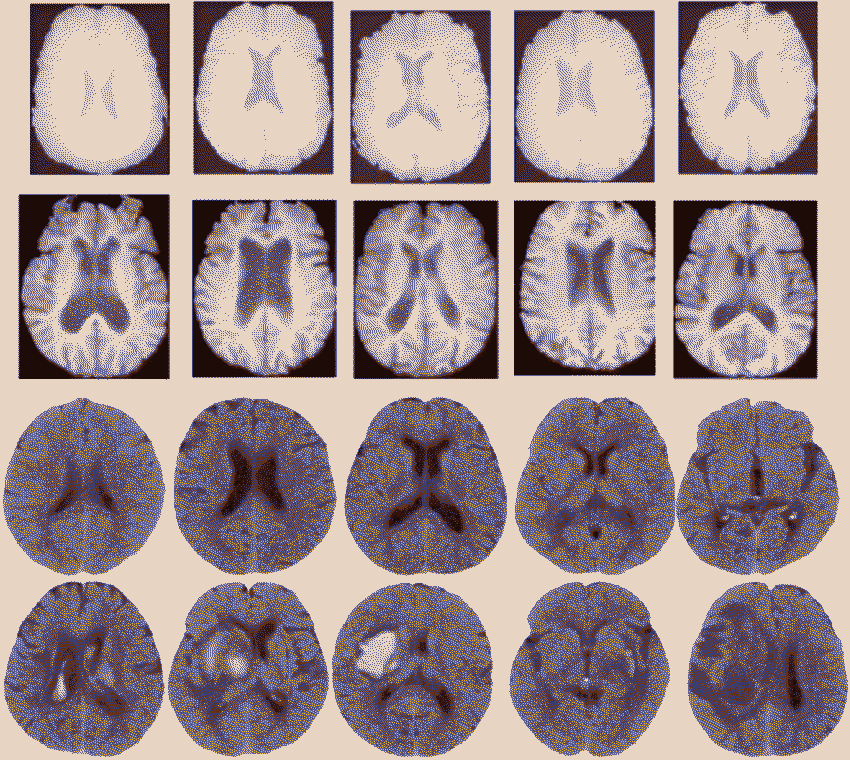

Brodmann area 7 is the intersection of the vision and propRioception functions of the brain, used primarily to locate objEcts in relation to the body. It also plays a role in language speaking, possibly to define the concepts of objects and their Conscious construction. The cross between self-perception and outer-perception makes thIs area of the brain a gOod candidate for study regarding the possibility of psychic powers, especially regarding 'telekinesis' (which may emerge with special synesthesia intermixing vision and proprioception, enabling an individUal to consider outside objectS as a part of their internal body).

The splenium of the corpus callosum

The cingulate gyrus